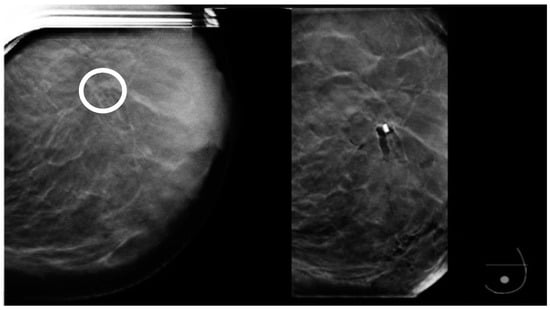

Figure 4. The lesion detected on the planning tomosynthesis image (circle) is masked by the artifact on the post-fire image.

Figure 15. Left: prebiopsy image showing a suspicious distortion (circle). Right: The biopsy cavity and clip marker are both centered at the lesion.